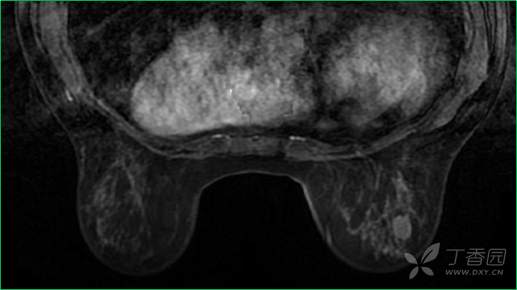

T1WI增强早期

乳腺MR:左乳外上象限见T2WI高信号肿块影,大小约12mm×10mm×13mm,肿块为卵圆形,边缘模糊不规则;内部强化略不均匀;TIC曲线初始相呈快速强化,延迟期呈平台型;DWI呈高信号,ADC值为 0.000698 mm2/s。

因肿块边缘不规则,内部强化不均匀, TIC曲线初始相呈快速强化,延迟期呈平台型;DWI呈高信号,ADC值较低,考虑左乳外上象限肿块恶性不除外,BIRADS 4类。